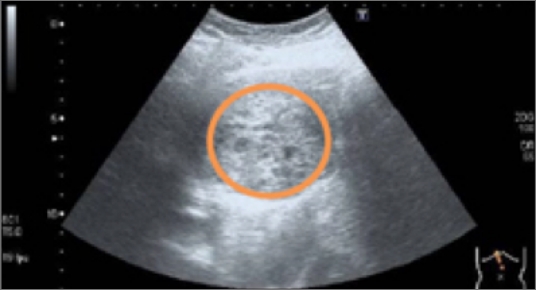

• 検査のイメージ

膵癌